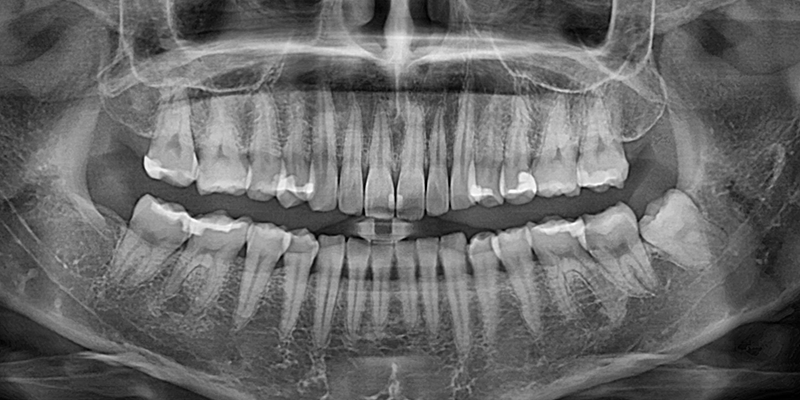

Before X-ray

ការថតរូប X-ray មុនការវះកាត់

កំណត់ទីតាំងនៃធ្មេញស្រលាញ់យ៉ាងត្រឹមត្រូវដោយការថតរូប X-ray.